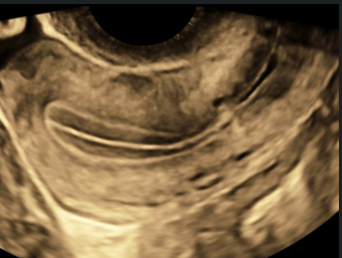

Sonohysterography and Hysterosalpingo-Contrast Sonography (2021)

This topic focuses on sonographic imaging of the female pelvis that includes the uterus and ovaries and, when appropriate, the fallopian tube.